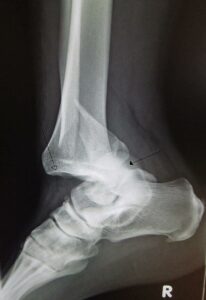

ارتوپدی پا یکی از شاخههای مهم و کاربردی علم ارتوپدی است که به تشخیص، پیشگیری، [...]

شکستگیها و دررفتگیها از جمله آسیبهای شایع ارتوپدی هستند که میتوانند هر کسی را در [...]